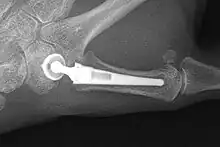

Joint Replacement

X-ray of trapeziometacarpal joint replacement. Left hand of a 58-year-old woman.

The joint can be replaced with artificial material. An artificial joint is also referred to as a prosthesis. Prostheses are more problematic at the trapeziometacarpal joint compared joints like the knee or the hips.

[27]Prostheses come in many varieties, such as spacers or resurfacing prostheses.

It’s not clear within the current literature that a prosthesis has any advantage over trapeziectomy.[27]

Overall, joint replacements are related to long-term complications such as subluxation, fractures, synovitis (due to the material used) and nerve damaging.[35] In many cases revision surgery is needed to either remove or repair the prosthesis. Also note that usage of a joint replacement is heavy in costs.

The quality of the prostheses is improving and there is reason to believe this will have a positive effect on outcome in the years to follow.[27]